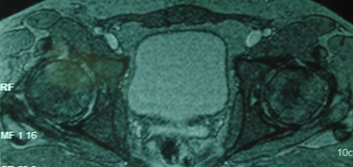

Имя     : ЯМР 2 май 2009.JPG

Тип     : image/jpeg

Размер  : 38885 байтов

Описание: отсутствует

Url     : http://weborto.net:8080/pipermail/ortho/attachments/20090520/789da7ae/attachment-0002.jpeg